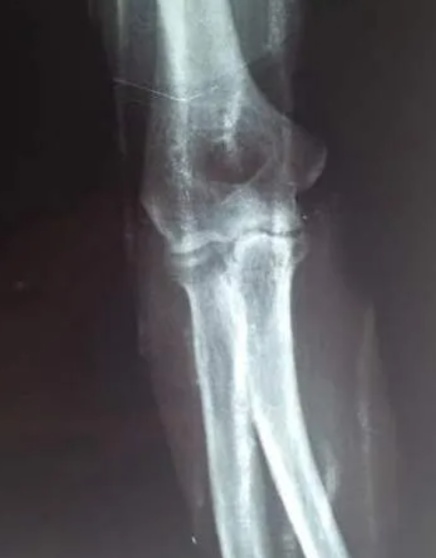

Figure 1. Pre-reduction X-ray image of ulnar coronoid fracture

1. 冠骨折复位前X线图像

患者,男,50岁,于2024年7月踢球运动中跌倒后出现右肘及右腕部肿胀疼痛伴活动受限就诊。骨科检查:一般情况好,神清,右肘皮肤有轻度擦伤,右肘关节肿胀,屈伸活动严重受限,被动活动时疼痛加重。肘关节x线检查提示:右侧尺骨冠状突局部骨皮质撕裂,可见多个小骨碎片并有移位,肘关节不全脱位,右侧桡骨小头和右侧肱骨远端未见骨折征象,右侧尺骨冠突骨折(见图1)。诊断:尺骨冠突骨折。治疗方法:1. 门诊以行手法复位,复位手法:前臂旋后位,一手扶患肢肘部,拇指置肘窝,摸清向上移位骨折块,垂直向下按压,同时屈曲肘关节,使前臂旋后,屈肘100˚位肩肘带固定于胸前。复位后患者自觉肘关节疼痛较前明显减轻,遂行x线复查可见尺骨冠突对位对线情况良好(见图2)。2. 局部金黄膏外敷消肿止痛[3],日更换一次。制动2周后行肘关节行屈伸功能锻炼,局部中药透入治疗。